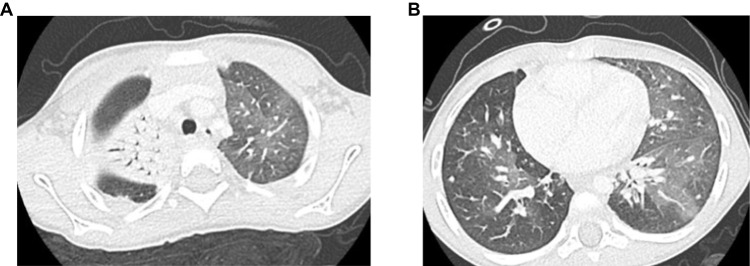

Results: We present the case of a 3-year-old boy with a history of recurrent viral-induced wheezing, initially treated for asthma-like symptoms until he developed persistent hypoxemia. Despite targeted therapy, the patient exhibited persistent respiratory symptoms and consolidative opacities in the right lung. A high-resolution computed tomography (HRCT) scan showed diffuse lung abnormalities, prompting further evaluation. Bronchoscopy with bronchoalveolar lavage revealed Haemophilus influenzae infection, and an open lung biopsy confirmed AFOP. The patient was treated with corticosteroids and azithromycin, leading to significant clinical and radiographic improvement.